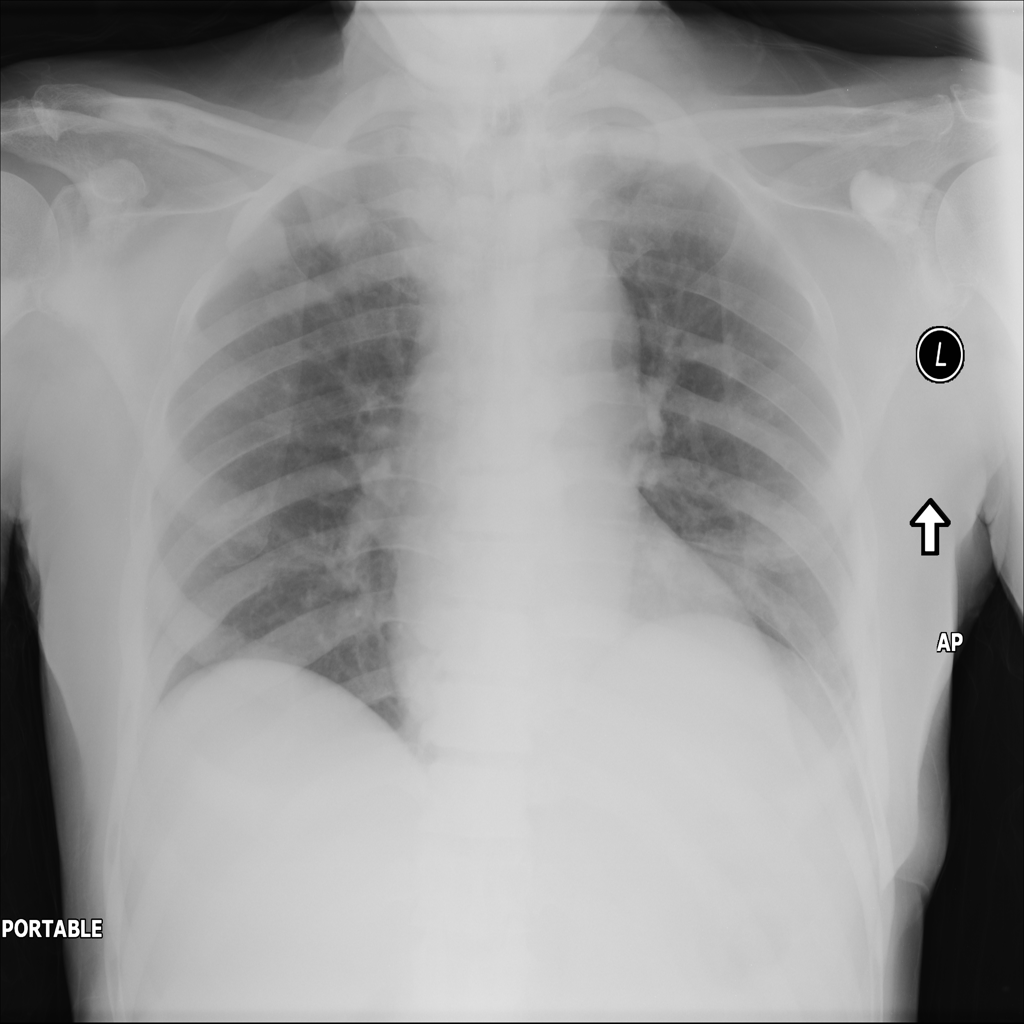

PAT-B9C3 · IMG-000Atelectasis

PAT-B9C3 · IMG-000

AP